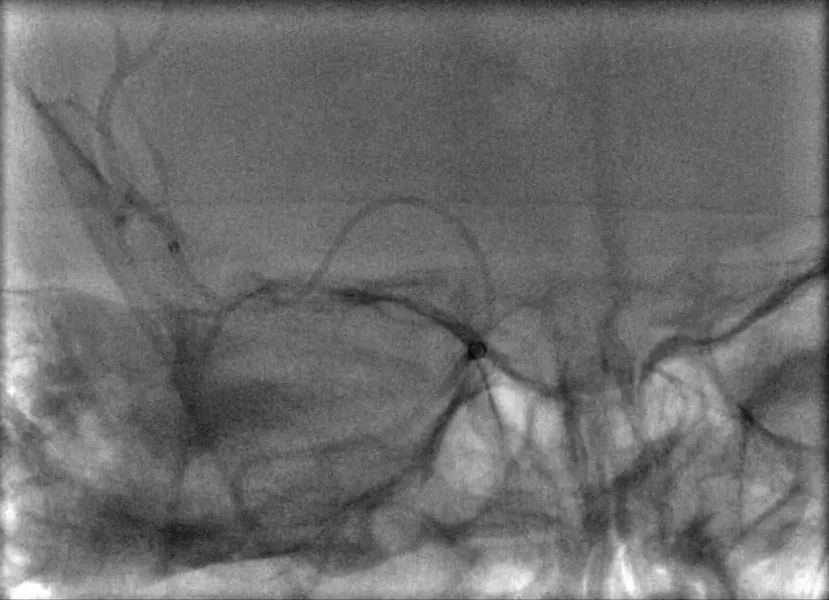

最后双支架联合抽吸拉通血栓。造影提示取栓后血管再通,TICI 3级。

造影提示取栓后血管再通,TICI 3级(A);抽吸联合取出的血栓(B)